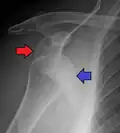

In over 95% of shoulder dislocations, the humerus is displaced anteriorly.[8] In most of those, the head of the humerus comes to rest under the coracoid process, referred to as sub-coracoid dislocation. Sub-glenoid, subclavicular, and, very rarely, intrathoracic or retroperitoneal dislocations may also occur.[9]

An anterior dislocation of the shoulder

Anterior dislocation of the right shoulder. AP X ray -